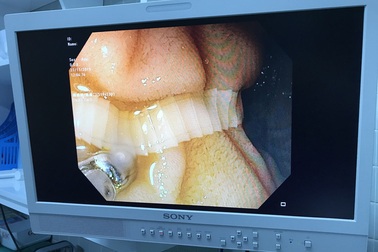

Vất vả lôi con sán dài cả thước trong người đàn ông quen ăn bò táiMột người đàn ông có thói quen ăn bò tái, đã bị nhiễm sán dài hơn 1 m, vừa được các bác sĩ vất vả mới lôi ra hết được

Kinh hãi sán xơ mít dài hơn 2m trong bụng bệnh nhânBệnh viện Hữu nghị Đa khoa Nghệ An đã thực hiện ca xổ thành công sán xơ mít tồn tại trong cơ thể bệnh nhân suốt nhiều năm.